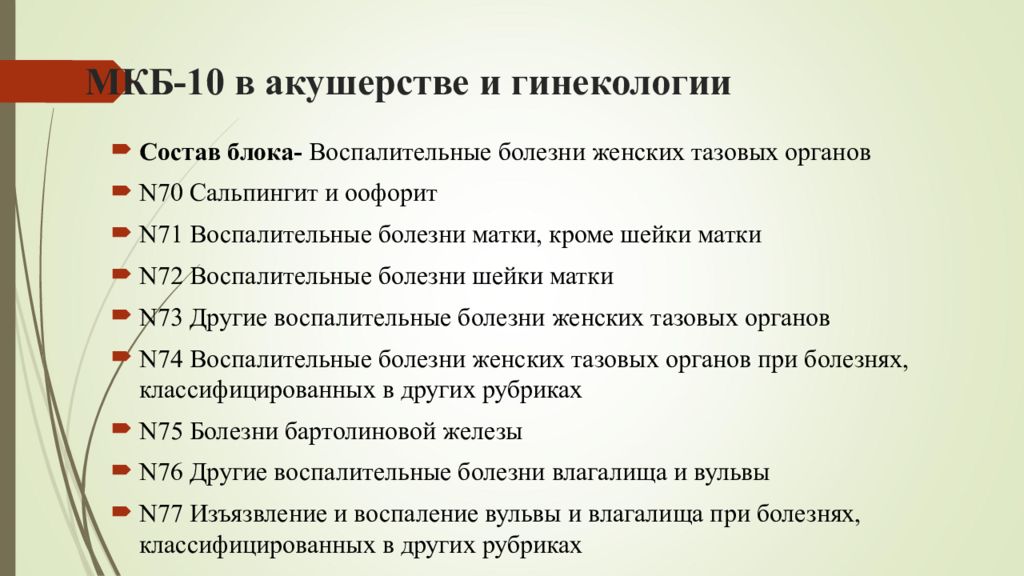

Острая внебольничная пневмония по МКБ-10: признаки и примеры